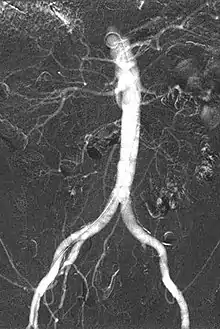

Carbon dioxide angiography is a diagnostic radiographic technique in which a carbon dioxide (CO2) based contrast medium is used - unlike traditional angiography where the contrast medium normally used is iodine based – to see and study the body vessels.[1] Since CO2 is a non-radio-opaque contrast medium, angiographic procedures need to be performed in subtraction angiography (DSA).

Carbon dioxide is a negative contrast medium and it has a low radiopacity (while iodinated contrast media are defined as positive contrast media due to their high radiopacity). Contrast is caused by the different X-ray absorption coefficients between the tissue and the contrast agent. In the vascular imaging results produced using CO2, vessels look brighter rather than the surrounding tissues, because the contrast medium absorbs less X-ray radiations rather an iodine-based contrast medium, where the vessel are displayed in black.

The CO2 does not mix with blood. At atmospheric pressure CO2 is in gaseous form and, when it comes out from the catheter, it forms a train of bubbles which displaces blood, causing a transient ischemia, in relation to the bloodstream (systolic pressure). When added together by DSA “stacking” software,[5] the result is a composite diagnostic image of the frames.